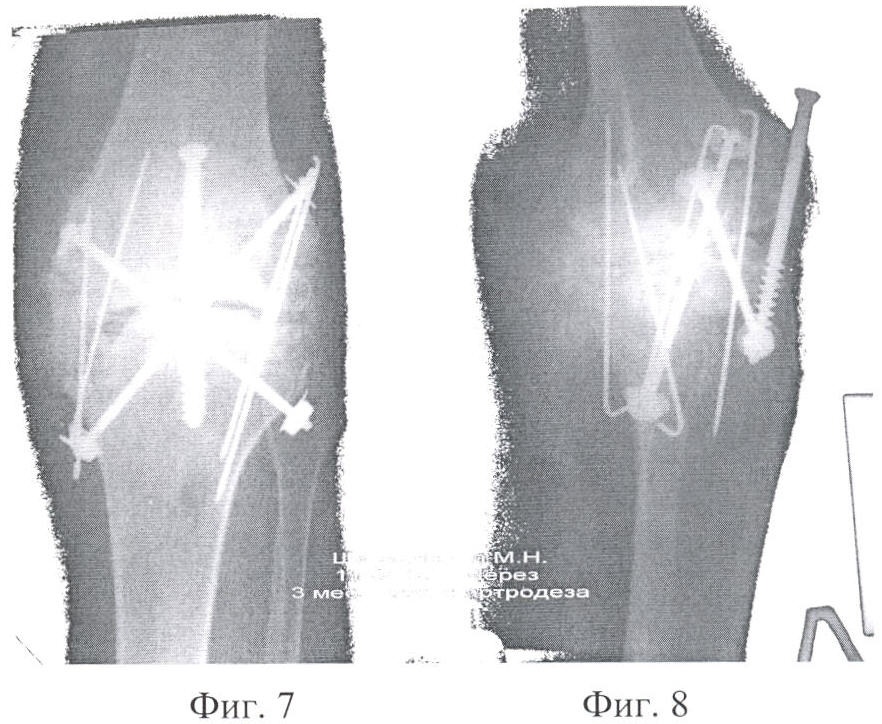

Фиг.7 – Контрольная рентгенограмма коленного сустава после артродеза заявленным способом (с двух сторон сустава) и остеосинтеза трансплантатов спицами в прямой проекции.

Фиг.8 – Контрольная рентгенограмма коленного сустава после артродеза заявленным способом (с двух сторон сустава) и остеосинтеза трансплантатов спицами в боковой проекции.

Способ оперативного вмешательства осуществляется следующим образом. До операции планируется диаметр фрезы, который должен быть не менее половины ширины суставной щели со стороны оперативного вмешательства, при этом большая часть трансплантата планируется выпиливать со стороны суставной поверхности, имеющей меньший дефект. На фиг.9 и 10 меньший дефект имеет мыщелок бедренной кости. Больной укладывается на операционном столе. Обрабатываются кожные покровы, как перед операцией. На конечность накладывается жгут с целью обескровливания операционного поля. Производится послойный доступ к суставу (ложному суставу). При необходимости производится коррекция вальгусной или варусной деформации сустава с временным фиксированием его спицами. Место для введения цилиндрической фрезы особо не готовится, т.е. не иссекаются связки, рубцы и надкостница. Цилиндрической фрезой выпиливается на заранее запланированную (фиг.1, фиг.2) глубину два разновеликих трансплантата (больший трансплантат берется из менее травмированной кости, имеющей меньший дефект). Оба трансплантата извлекаются или сразу же разворачиваются в образовавшемся туннеле так, чтобы полностью заполнился дефект в кости и перекрыл зону ложного сустава. Импактором по торцу введенных трансплантатов наносятся удары (трансплантаты вбиваются) с целью слегка расширить их («смять», чтобы они плотно сели на место) и сразу же производится остеосинтез каждого трансплантата спицей или винтами, или же винтом обоих трансплантатов с одновременным фиксированием сустава (фиг.5). Вслед за трансплантатами укладываются оставшиеся костные фрагменты или они вбиваются между трансплантатами (если они есть, например, срубленные остеофиты) и рана послойно зашивается до дренажа. Затем производится дополнительная иммобилизация гипсовой повязкой на срок до трех месяцев в зависимости от анатомической области оперативного вмешательства.